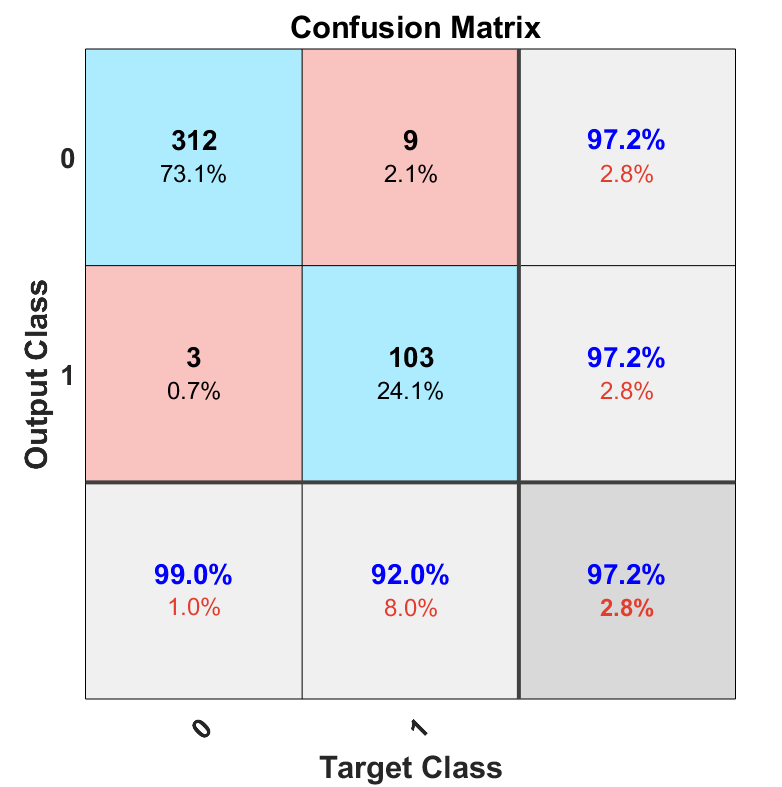

Fig. 2 shows the confusion matrices of leave-one-out quadratic SVM with augmentation on the right side versus no augmentation on the left side. By applying the augmentation method, not only did the total accuracy increase slightly to 97.2% but also the false negative (folded patch, but classified as normal patch) also decreased from 2.6% to 2.1%. However, the false positive (normal patch, but classified as a folded patch) remained unchanged. In general, any type of error is not desirable, nevertheless, in our case, false positive might be preferred over false negative.